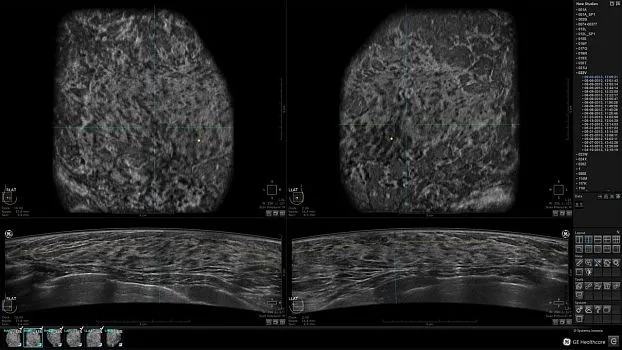

Клинические изображения

• Получение объемных 3D изображений с возможностью покадрового просмотра

• Отображение объемных 3D ультразвуковых изображений, которые состоят из традиционных поперечных и воссозданных коронарных и сагиттальных проекций

• Многооконный просмотр: 4 - 12 изображений.

• Изменяемая толщина среза: 0,5 - 10,0 мм (шаг 0,5 мм)

• Настройка градаций серого

• Функция панорамирования и масштабирования

• Инструмент увеличения 4X